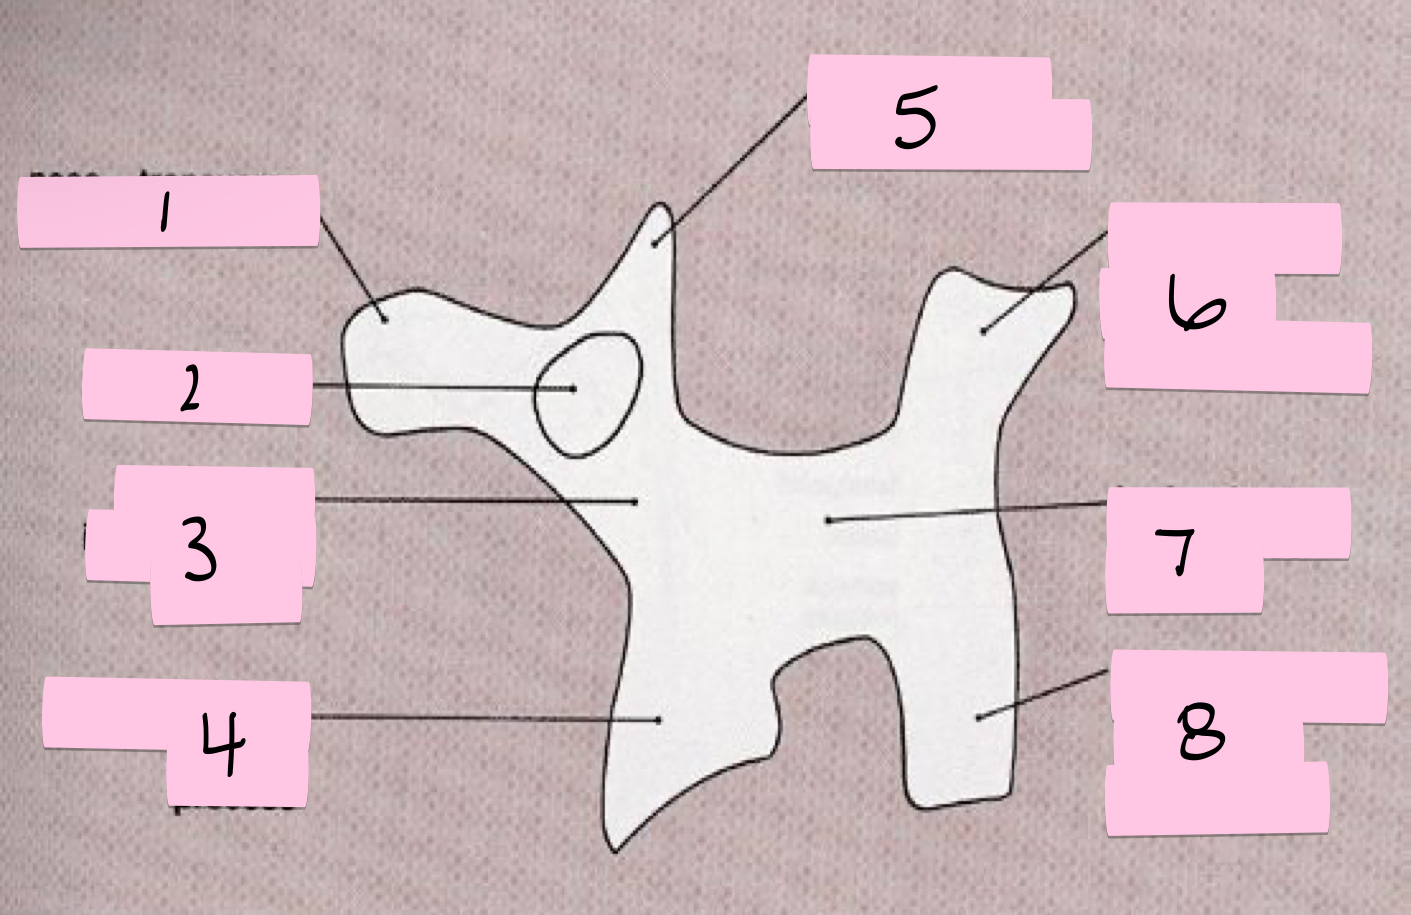

What is 1 pointing to?

Nose- Transverse process

What is 2 pointing to?

Eye- Pedicle

What is 3 pointing to?

Neck- Pars interacticularis (isthmus)

What is 4 pointing to?

Foreleg- Inferior articular process

What is 5 pointing to?

Ear- Superior articular process

What is 6 pointing to?

Tail- Superior articular process of opposite side

What is 7 pointing to?

Body- Lamina and spinous process

What is 8 pointing to?

Hindleg- Inferior articular process of opposite side